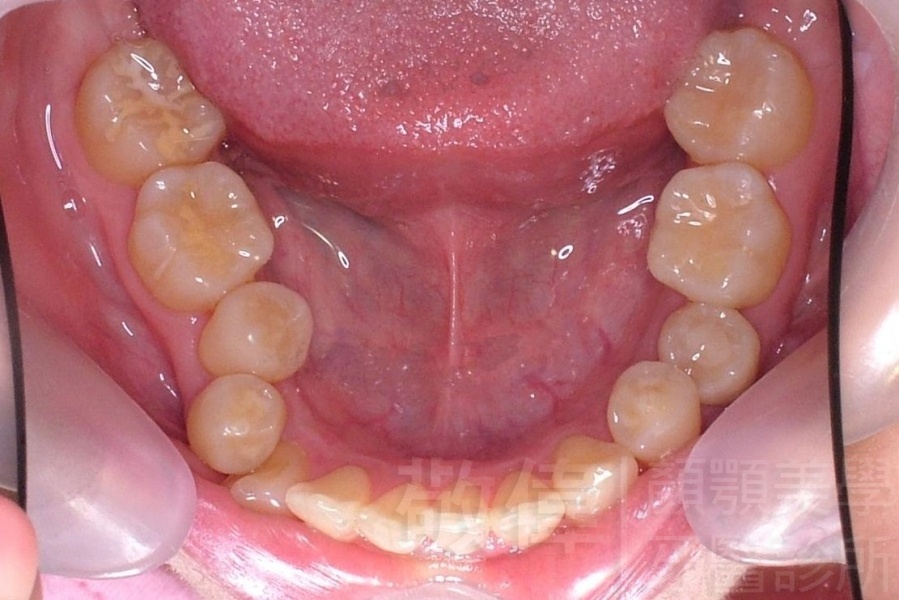

矯正前-上   矯正前-下

矯正後-上   矯正後-下

上顎暴牙且牙齒極度混亂,經由矯正之後,臉型大幅度改善,牙齒的排列更加的整齊健康。相較於之前眼神充滿精神,自信心展現無遺。